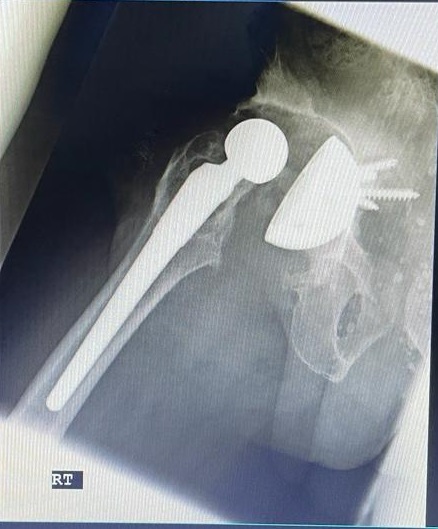

71-year old male with a right total hip following fracture dislocation 21 years ago presents with a 6 month history of increasing pain and shortening of the right lower limb. Recommended for acetabulum revision. Performed with graft multi hole revision cup and change of femoral head to 36 mm